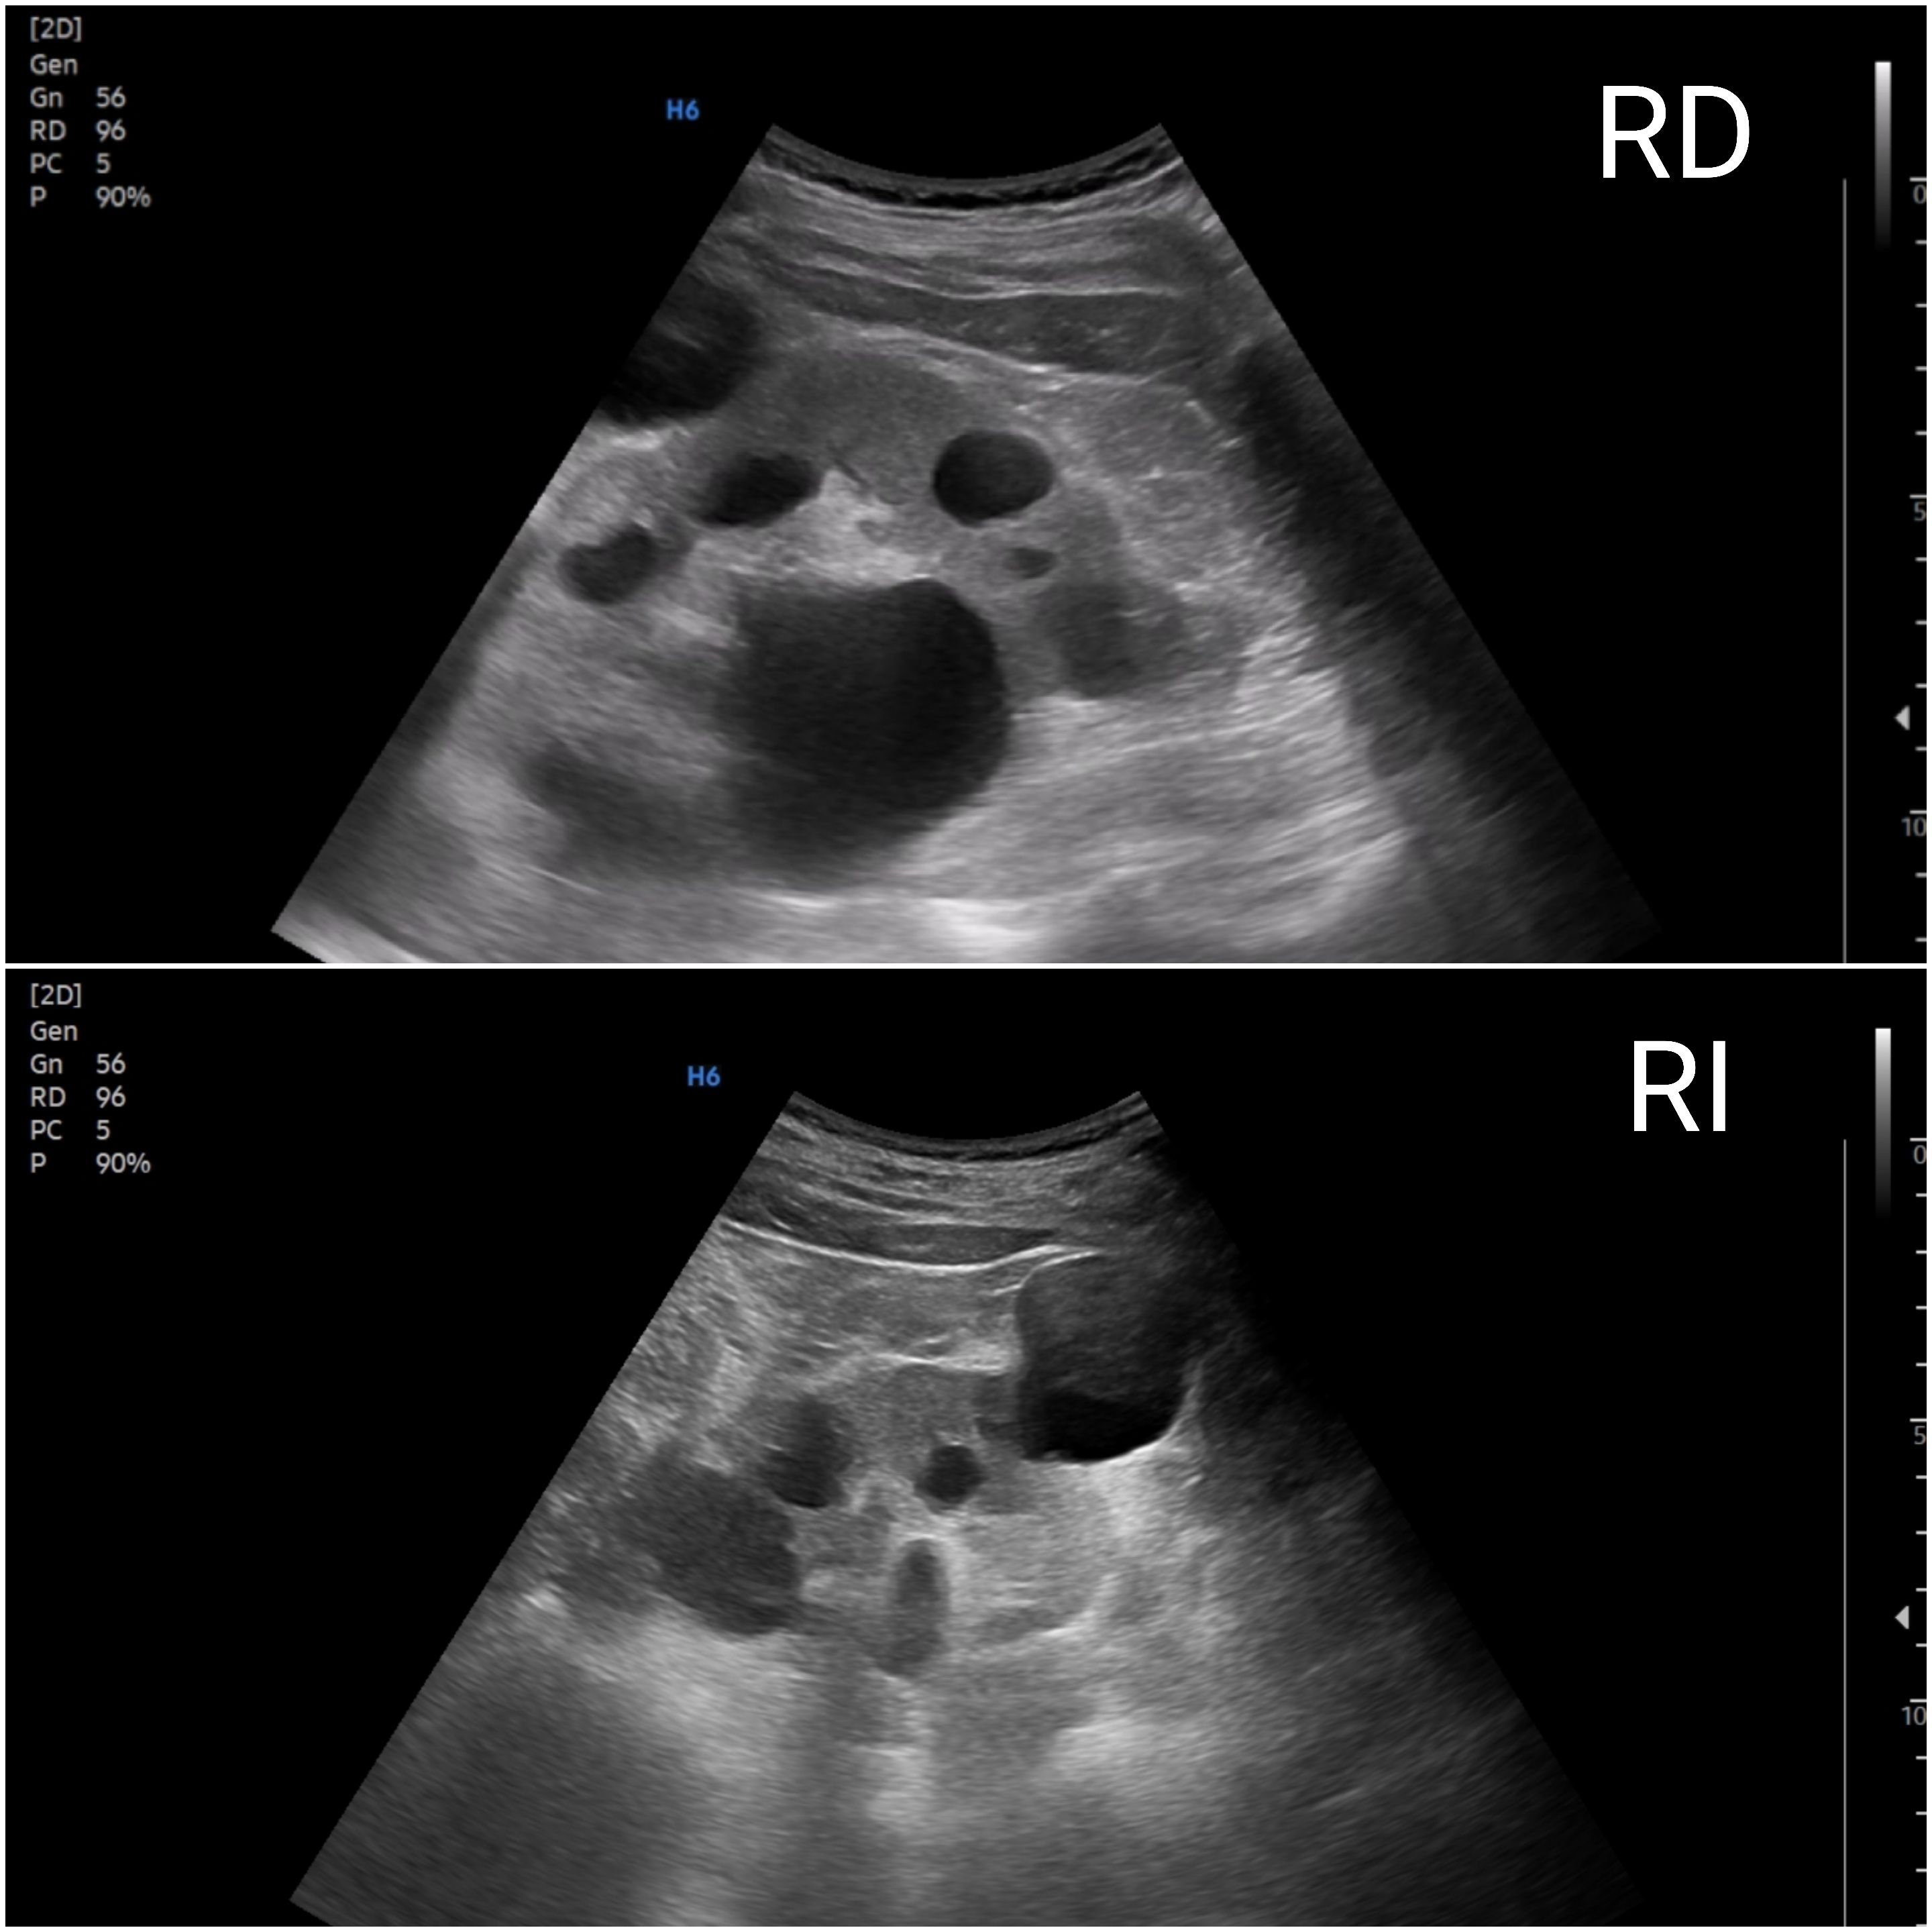

Ecografía: Próstata de 25 cc, sin lesiones intravesicales. Riñones de tamaño conservado con múltiples quistes bilaterales de varios tamaños, con criterios de quistes simples (anecoicos, pared fina, sin septos ni componente sólido, con refuerzo posterior), en número de más de cinco por cara riñón. Aorta abdominal de calibre aumentado a nivel epigastrio 35 mm llegando a 39 mm porción más distal. Aumento de calibre de ambas ilíacas.

Enfermedad poliquística probable PQRAD Enfermedad Poliquística Renal Autosómica Dominante.

Hallazgo de aneurisma de aorta abdominal (AAA) en paciente con enfermedad arterial periférica y alto riesgo cardiovascular. El diferencial ecográfico incluye ectasia aórtica y sobrestimación por tortuosidad/planos oblicuos. Deben buscarse los signos de disección. Los quistes renales se clasifican como simples, diferenciándolos de quistes complejos y masas sólidas, pero en varón de 66 años siendo más de 5 en cada riñón obligan a pensar en la enfermedad poliquística.